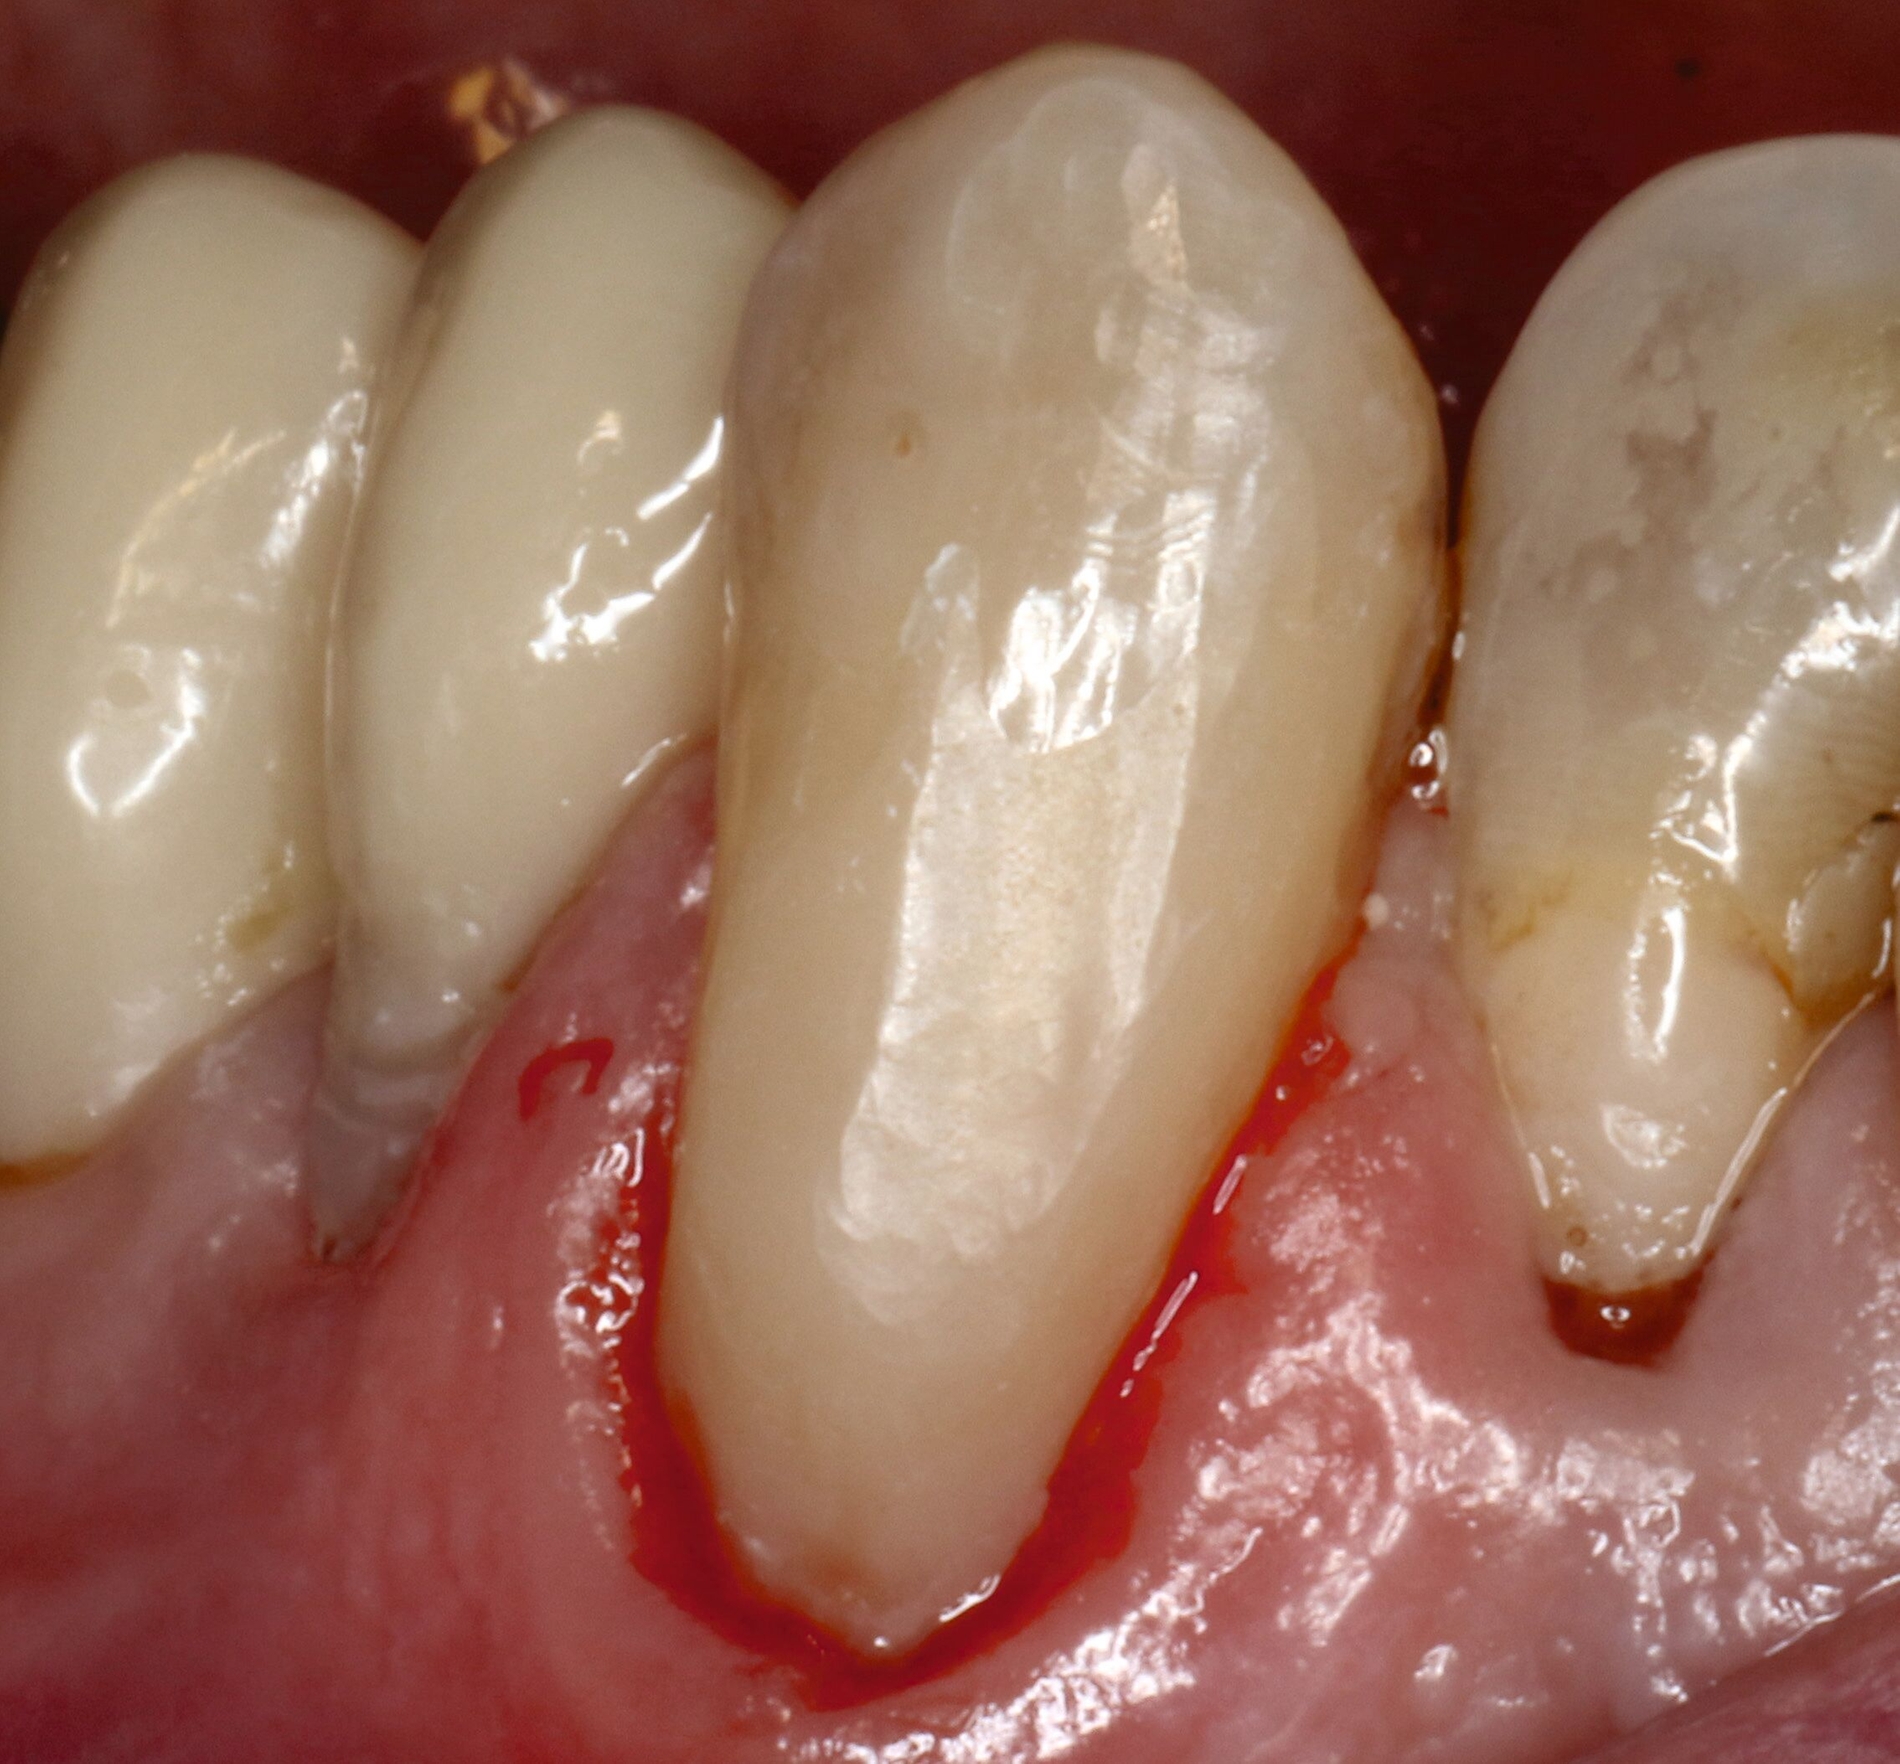

Wurzelkaries kann alle Bereiche der Wurzeloberfläche betreffen und ist in der Regel an Plaqueretentionstellen etwa im Bereich des Gingivarandes, der Kronenränder, der Einziehungen der Wurzeloberfläche oder des Interdentalraums lokalisiert. Zur klinischen Diagnostik sollte zunächst Plaque möglichst vollständig entfernt werden, um interdentale Bereiche einsehen und aussagefähig sondieren zu können. Während die Oral- und die Vestibulärflächen relativ einfach zu befunden sind, sollten die Interdentalräume unter guter Trockenlegung und Ausleuchtung beurteilt werden. Bei ausgedehnten Rezessionen ist die Diagnostik auch interdental gut möglich (Abbildung 4).

Für die Therapieentscheidung ist es essenziell, zwischen aktiven und inaktiven Läsionen zu unterscheiden (Abbildung 6). Die Farbe der Läsion ist zwar kein verlässliches Diagnosekriterium, aktive Wurzelkaries hat aber eher eine gelbliche oder hellbraune Farbe, ist in der Regel von Plaque bedeckt und fühlt sich bei mäßigem Sondieren weich oder ledrig an. Solche Läsionen bedürfen einer Intervention. Inaktive oder arretierte Läsionen haben in der Regel eine dunklere Farbe, sind meist plaquefrei und fühlen sich bei Sondieren hart an. Inaktive Wurzelkaries braucht keine weitere Intervention, auch wenn sie kavitiert, aber reinigungsfähig ist. Die Patientinnen und Patienten sollten jedoch über solche Befunde aufgeklärt werden.